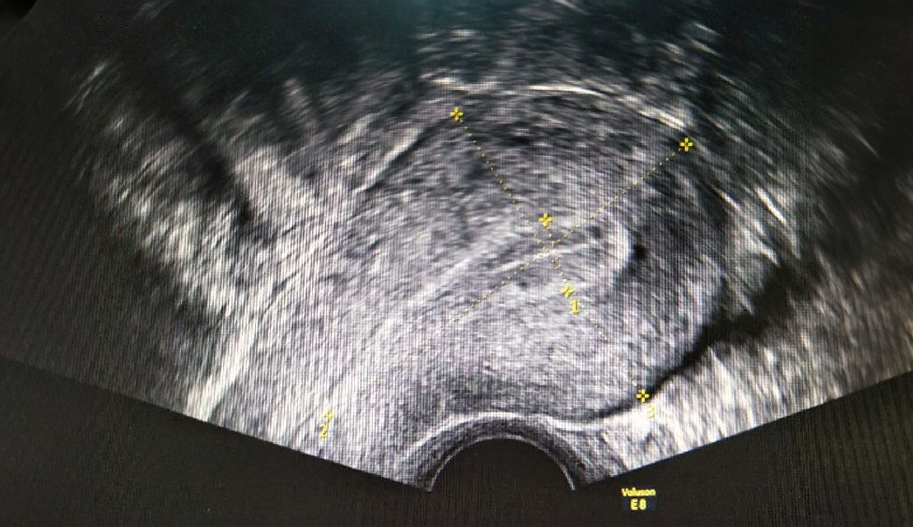

Transvaginal Color Doppler Ultrasound

Ultrasound is an integral part of modern gynecological examination. Transvaginal ultrasound has allowed for a much more detailed examination of gynecological physiological and pathological processes by evaluating the organs of interest more closely with a high-frequency probe. In addition to the gray-scale views of the ovaries and endometrium, which change throughout the menstrual cycle, the use of Doppler allows for the evaluation of blood flow in these organs. Moreover, most pathological processes result in changes to the normal vascular pattern. It is important to distinguish these changes from the physiological neovascularization that occurs in the ovary around the follicle developing during each menstrual cycle.

Transvaginal scanning allows for a closer evaluation of pelvic vessels, particularly facilitating the visualization of the ovarian artery.

The area of interest is first identified on gray-scale ultrasound. Color Doppler uses a color box, the size of which should be adjusted to fit the size of the area being examined.